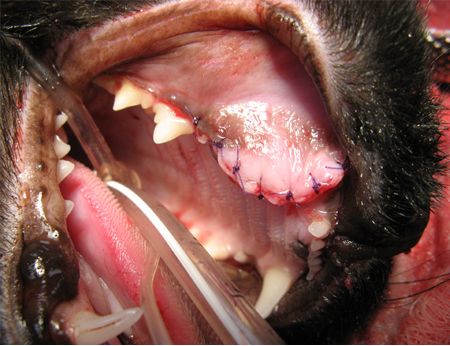

The surgical approach to resolution in this case involved a mucogingival flap to expose the underlying bone (Photo 3). Clear fluid exuded from the ventral aspect of the initial incision. The exuberant bone was removed with a dental bur, and the defect was enlarged to aid in visualization.

Photo 3: A mucogingival flap has been created to expose the underlying bone.Cyst material was then removed in pieces with the aid of a periosteal elevator, thumb forceps and a hemostat (Photo 4). In this patient, the progressive growth of the cyst expanded the vestibular bone and overlying gingiva to produce the mass effect. The lateral wall of the nasal cavity was compromised. The palatal wall of the infraorbital canal wall was obliterated, exposing the infraorbital neurovascular bundle.

Treatment for dentigerous cysts involves removal of the cyst lining and the tooth while avoiding vital structures within the bone. Any teeth in which the apex has been compromised should be extracted. Teeth in which the apex is preserved but cementum is destroyed may be salvageable but must be followed radiographically to ensure viability. In this case, suction, surgical magnification, and meticulous cyst removal was vital around the infraorbital vasculature and nerves.

Photo 5: The tip of the suction wand can be seen here at the caudal extent of the cyst's expansion.Once cyst excision and extraction were complete, a postoperative radiograph confirmed complete removal of the tooth, and the mucoperiosteal flap was trimmed and sutured in a simple interrupted pattern with 4-0 absorbable monofilament suture material (Photo 6).